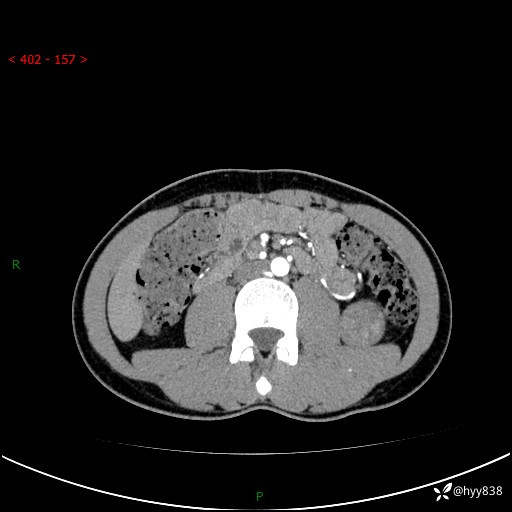

现病史:患者昨日中午进食后出现明显腹痛,腹泻,在我院急诊科行补液及对症治疗,双肾输尿管彩超提示左肾占位(5.2*4.3cm),平素无明显腰痛,无再发肉眼血尿等情况,现为求处理左肾占位,遂来我院,门诊以左肾占位收治入院。 患者起病以来,精神、食欲、睡眠尚可,大便可,小便如上,体力体重无明显下降。

双肾CT平扫+增强(三期)